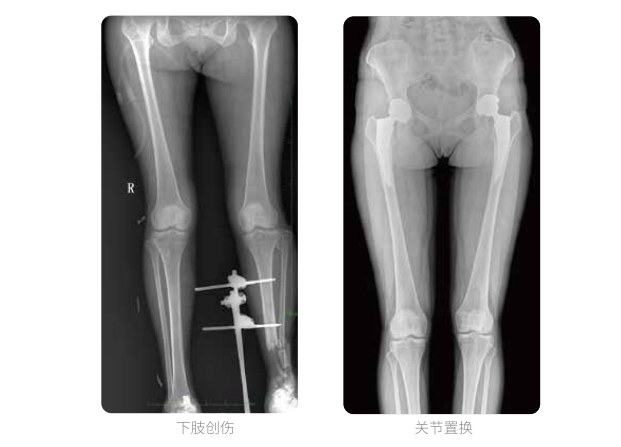

近年来,脊柱及下肢畸形的患者较多,多发于青少年的脊柱侧弯畸形,骨性关节炎、风湿性关节炎以及双下肢畸形如膝关节内外翻、X型O型腿等也是骨科常见病。并且发病率呈现逐年升高的趋势,常常累及下肢髋、膝、踝3个负重关节,影响患者生活,甚至丧失工作能力。

在脊柱及下肢畸形的临床治疗过程中,一般需要进行矫正手术治疗,在对其进行手术前后,均需要拍摄X光片以便分析病情、明确诊断和观察治疗效果。常规DR拍摄面积有限,最大规格仅有43cm,但成人男性全脊柱长度平均为70-75cm,女性为66-70cm,而双下肢更长。华体会体育登入首页PLX8600动态DR的43cm*86cm超大有效视野,可一次性拍摄全脊柱、双下肢的影像视野。

华体会体育登入首页动态数字化X线摄影(动态DR)拥有43cm*86cm超大有效视野,使全脊柱及双下肢能够得到完整清晰的成像,为临床在脊柱侧弯畸形和下肢骨关节病变诊断、治疗方案制定及治疗后复查提供精准的测量。

双下肢临床影像

华体会体育登入首页动态数字化X线摄影(动态DR)可以整体显示双髋至双踝关节,直观的展示因关节软骨磨损和软组织不平衡所造成的畸形及力线异常,全面对比了解双下肢的病变情况。对于下肢矫正和人工关节置换术的术前计划,术后观察有着重要的临床意义。

华体会体育登入首页动态数字化X线摄影(动态DR)一次成像不拼接,解决了拼接图像存在密度不均匀,拼接处图像配准和放大效应等问题,给临床带来了真正的大视野影像解决方案,高清画质,准确成像不失真,辅助医生准确诊断疾病。